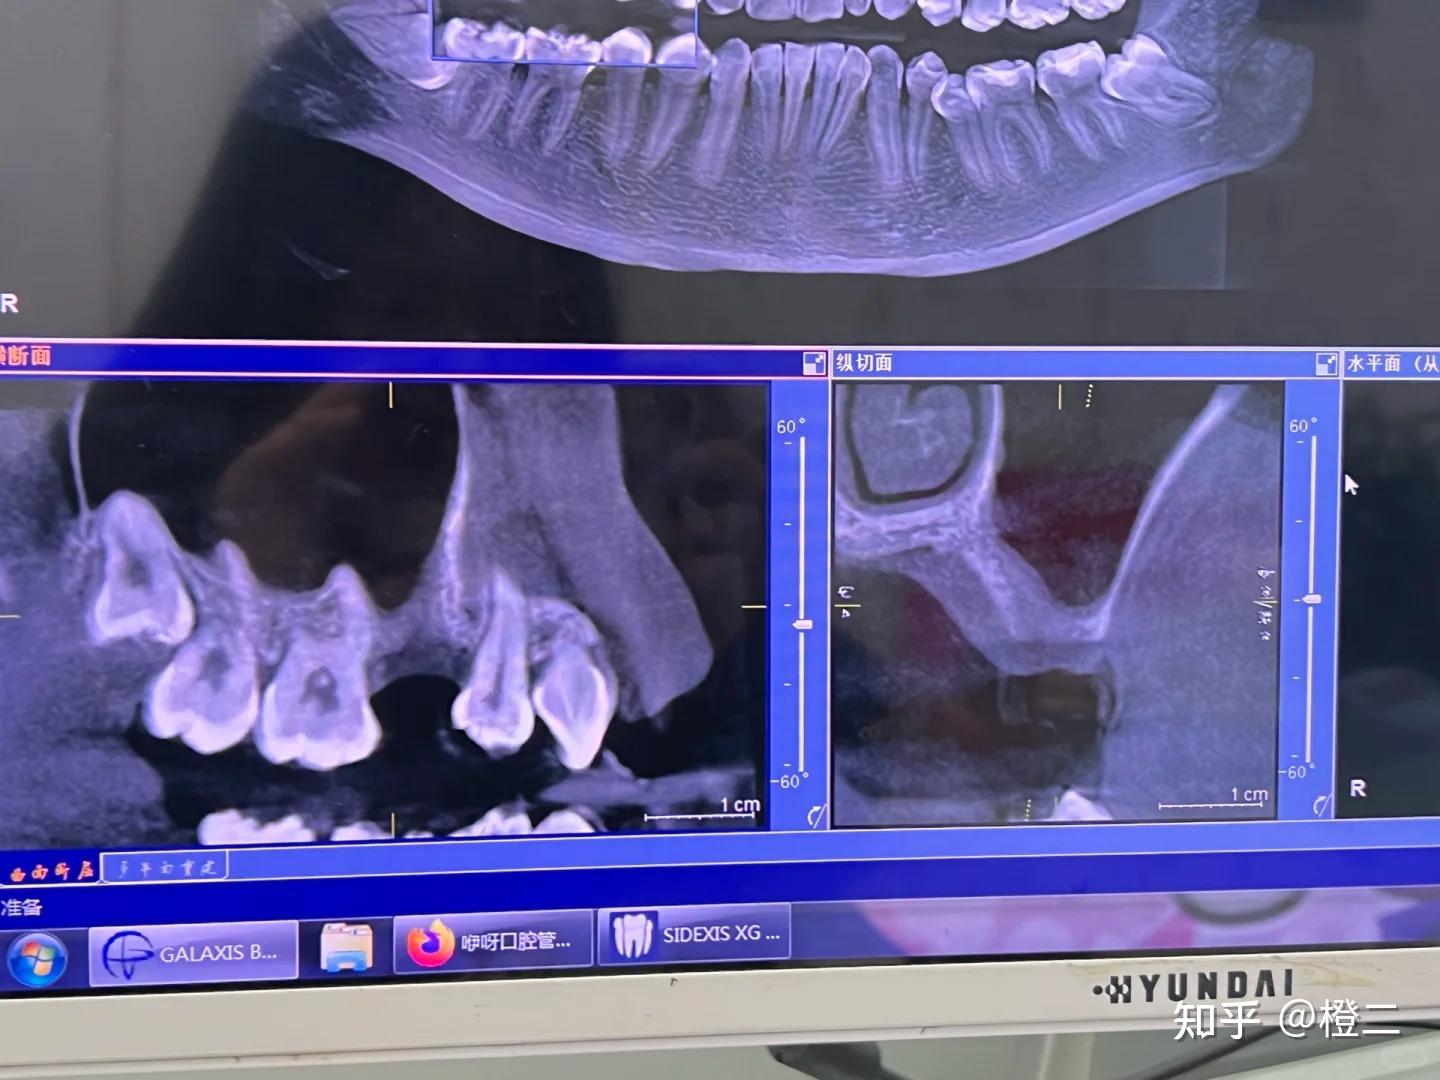

简单说说:哪些人需要骨粉?牙槽骨高度<8mm或宽度<5mm

上颌窦底骨质薄需内提升

具体大家可以对照牙片来看,拿不准也可以私信问我(ps:我纯粹是为爱发电,打赏全关了的,不会收你一分钱,但我也有自己的工作,没办法秒回,看见就回哈)

具体骨粉的价格体系,参考图片吧

骨粉材料:国产300-800元/g,进口800-1500元/g骨膜:1000-3000元/片手术费:1000-3000元(视复杂程度)当然,不同情况所需要的方案&价格也不一样,我按照24年市场价估计的,大家可以参考一下

轻度骨缺损:需0.5g骨粉+1片骨膜,总成本约2000-4000元重度骨吸收:需2-3g骨粉+2片骨膜,总成本约8000-1.2w元